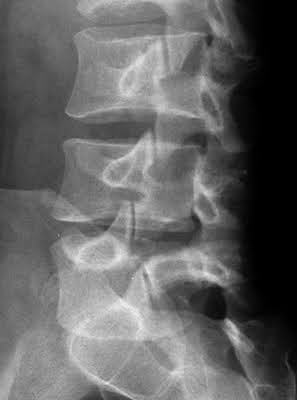

Name of condition seen in these images

https://photos.app.goo.gl/6sqJTrBaow6akuWD9

What is an anterolisthesis?